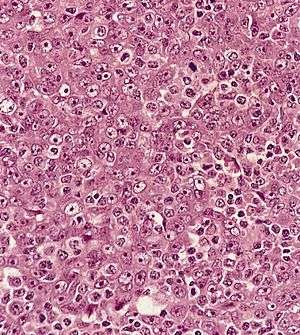

| Metastatic nasopharyngeal carcinoma in a lymph node | |

Undifferentiated nasopharyngeal carcinoma—low power

Undifferentiated nasopharyngeal carcinoma—med. power

Undifferentiated nasopharyngeal carcinoma—high power